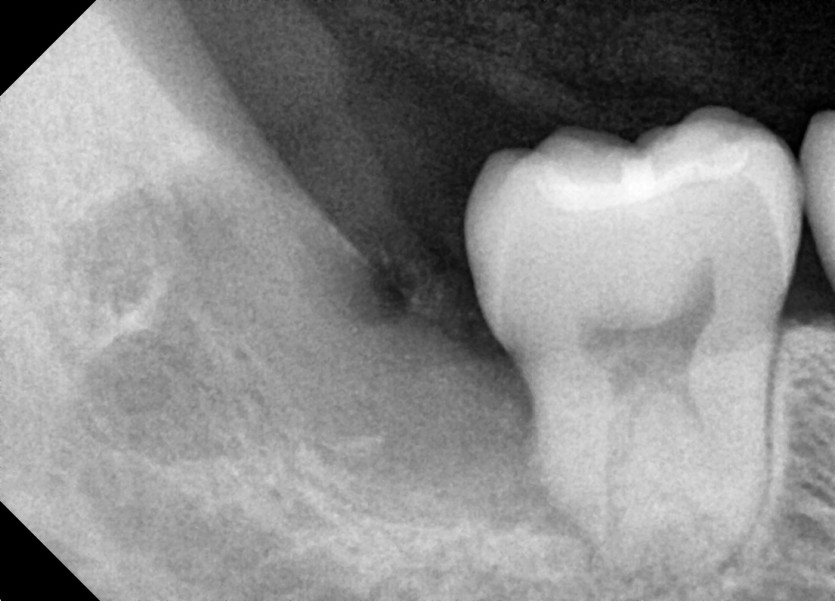

#38,48 사랑니 발치

구강 외과 전문의가 당일 발치했습니다.